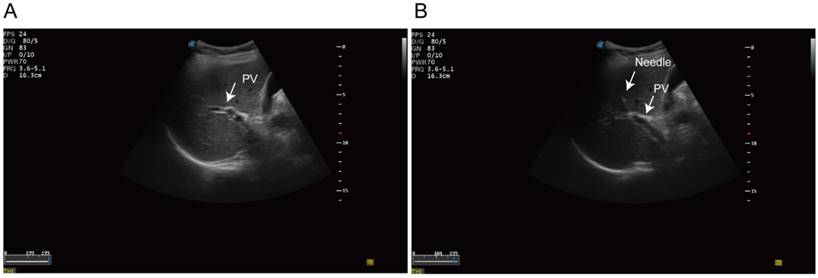

Fine-needle aspirates (FNA) biopsy was performed in standard procedure. Then we identified the intrahepatic portal vein under the ultrasonography guidance. A 20-guage needle was punctured into the portal vein trans-hepatically (Figure 1). 1 to 3 aliquots of 7.5 ml blood samples were aspirated from portal-vein and draw into 10ml Streck preservation tubes (Streck 218962, USA). Peripheral blood was then collected in parallel and processed identically. The blood sample was processed using the ClearBridge ClearCell FX systemTM (ClearBridge Biomedics, Singapore) [29]. Samples were further negatively sorted to remove the CD45 positive monocytes using EasySep™ Human CD45 Depletion Kit (18259RF, StemCell, USA). The identification of CTCs was based on immunofluorescence staining. CK19 or EpCAM positive cells was recognized as potential CTCs. Multicellular groupings of CTCs (CTC cellular ≥ 3) was considered as CTC cluster.

Figure 1

Ultrasonography-guided transhepatic puncture. (A) Identification of the portal vein under the ultrasonography guidance. (B) Transhepatic puncture of the portal vein using the 21 gauge needle.